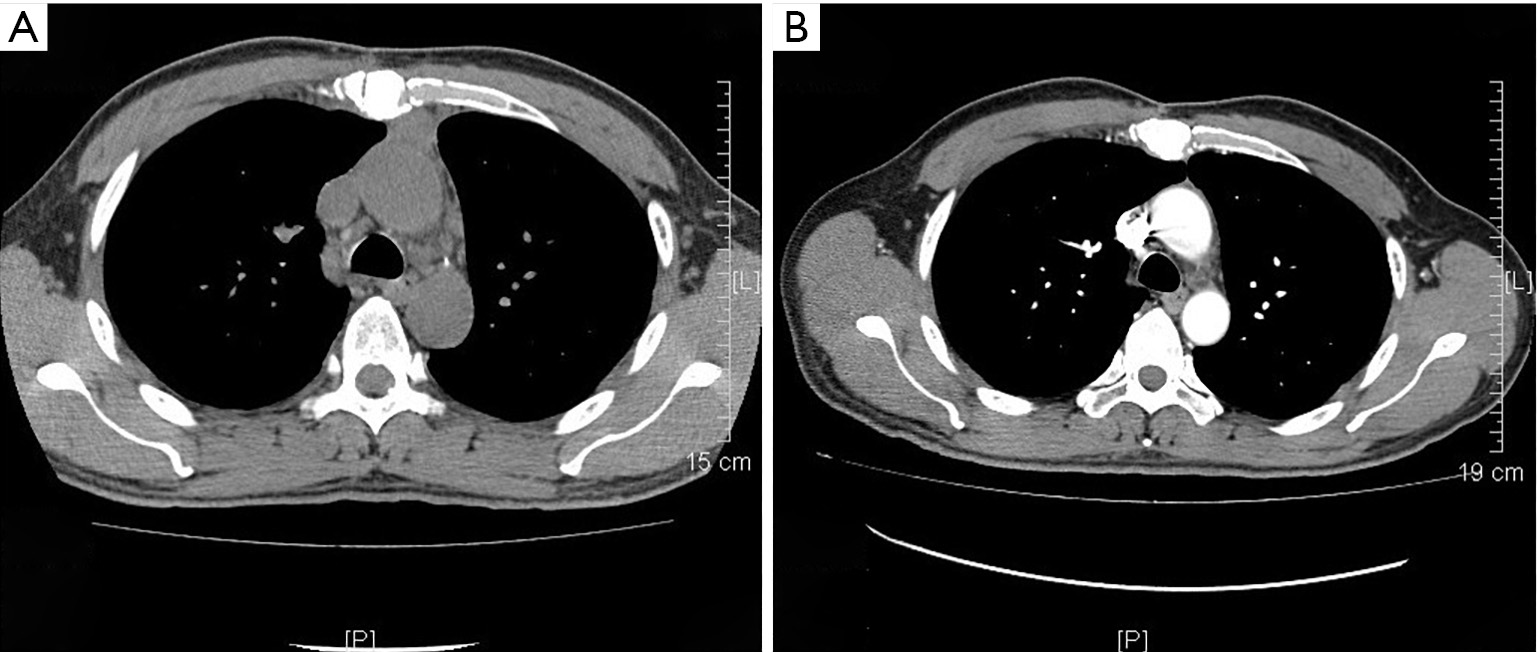

Thymic carcinoma presenting as atypical chest pain BMJ Case Reports

Thymic carcinoma presenting as atypical chest pain BMJ Case Reports Thymic Carcinoma Recurrence locally advanced thymoma and thymic carcinoma require a multimodality treatment approach with a combination of surgery,. the recurrence rates in stages i, ii, iii, and iv were 0.9, 4.1, 28.4, and 34.3 %, respectively; what the studies show. thymomas and thymic carcinoma are both thymic epithelial tumors (tets), but there are some important. in a. Thymic Carcinoma Recurrence.

Thymic carcinoma presenting as atypical chest pain Siddiqui et al Thymic Carcinoma Recurrence thymoma and thymic carcinoma treatment options include surgery, radiation therapy, chemotherapy,. in a thymic carcinoma, the tumors grow more quickly than thymomas and have a greater propensity for capsular invasion, metastases, and. what the studies show. thymoma and thymic carcinoma treatment options include surgery, radiation therapy, chemotherapy,. the recurrence rates in stages i, ii, iii,. Thymic Carcinoma Recurrence.